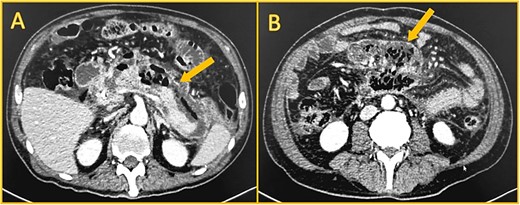

On the twentieth day, despite receiving carbapenem, the patient once again presented with a high fever. A subsequent computed tomography scan unveiled a capsulated peripancreatic collection measuring approximately 500 cc (Fig. 3). Using CT-guided percutaneous drainage, the collection was drained, and a pigtail was left in place. Nonetheless, the patient persisted with fever, was unable to eat, and suffered from hemodynamic instability. As the patient continued in a septic shock, and since endoscopic drainage was unfeasible due to our hospital limitations, the patient was scheduled for a laparoscopic necrosectomy. Intraoperatively, multiple dense adhesions were identified between the omentum, stomach, and anterior abdominal wall. The pancreas was meticulously debrided of necrotic tissue, and a drain was left. After surgery, the patient made a good recovery. The drain's amylase levels were negative for fistula. He had no fever or signs of shock. The drain had low and serous production, and he could eat solid foods without complications. On his thirtieth day, he was finally discharged and kept under close follow-up. Three months post-discharge, the patient was referred to the hepatobiliary center for definitive management of the ampulloma. He presented in good overall condition with adequate nutritional status. The procedure involved a pylorus-preserving pancreaticoduodenectomy and a Roux-en-Y reconstruction. The procedure was uneventful, and the patient's condition improved, and he was discharged without complication.

Shows contrast-enhanced computed CT. A: Large collection (arrow) anterior to the pancreas, with gas. B: Walled-off necrosis (arrow) with gas.